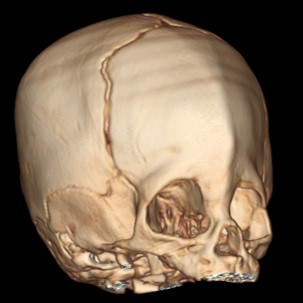

A craniossinostose ou cranioestenose é caracterizada pelo fechamento precoce de uma ou mais suturas cranianas (articulações fibrosas que conectam os ossos do crânio). A fusão precoce da sutura bloqueia o crescimento do crânio perpendicular à sutura afetada, ocorrendo um crescimento na direção da sutura acometida, resultando nesta deformidade estética.

Mas doutor, quando é preciso de tomografia do crânio? Quase nunca, é solicitado quando existe alguma dúvida e mais ainda nas craniossinostoses sindrômicas.

> Escafocefalia, é a sinostoses mais comum, vista mais no sexo masculino,o que acontece é o fechamento da sutura sagital levando o crânio ao formato de barco. A cirurgia é indicada de preferencia antes do sexto mês de vida, mas se a criança tiver mais idade, não impede de ser operado.

> Trigonocefalia, é o fechamento precoce da sutura metópica, o formato do crânio é em forma de pera o qual realiza compressão do lobo frontal que pode levar aumento da pressão intracraniana em até 20% dos casos. Crianças com mais de 5 anos que não foram operados, tem literatura que fala em dificuldade do aprendizado.

> Plagiocefalia, é o fechamento precoce da sutura coronal unilateral (plagiocefalia anterior) ou da sutura lambdoide (plagiocefalia posterior), afeta mais o sexo feminino e o lado direito é mais afetado. A criança tem um rostro em “arlequim” já que uma das órbitas esta retraída para cima e para tras.

> Braquicefalia, é o fechamento prematura de ambas suturas coronais ou lambdoides.